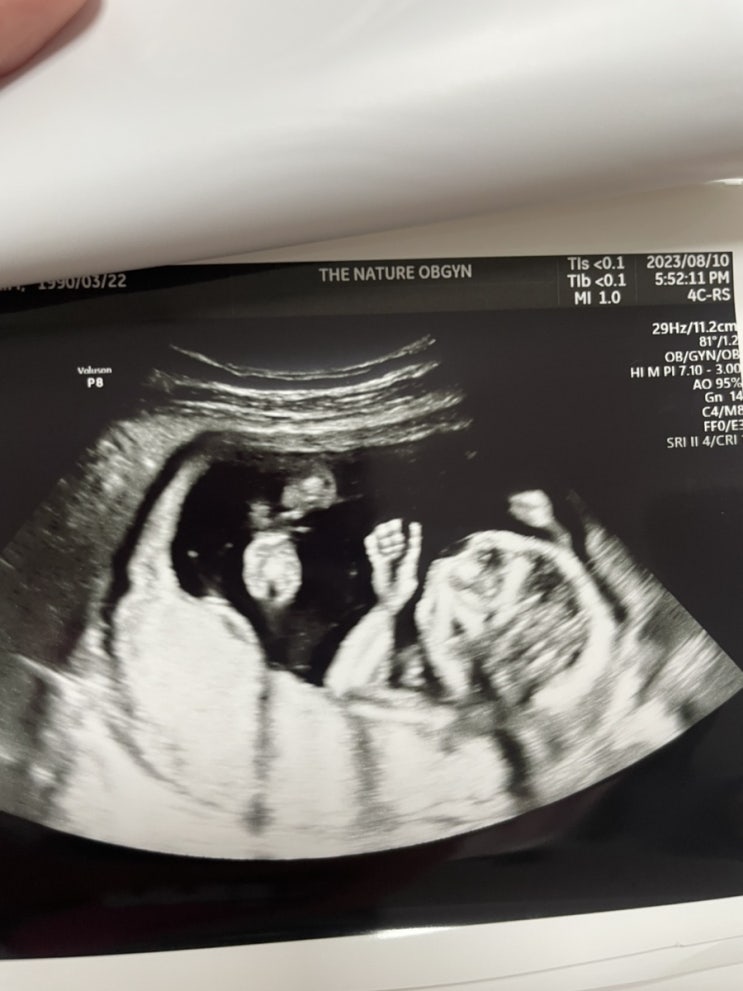

[임신일기] 임신 23-32주차 증상공유(임당통과, 첫 베이비페어, 오케스트라공연관람, 입체초음파, 기저귀가방 쇼핑, 만삭사진촬영)

[임신일기] 임신 19-22주차 증상공유(제주도 태교여행, 태동느낌, 에버랜드, 21주 정밀초음파, 늦은 조리원예약)